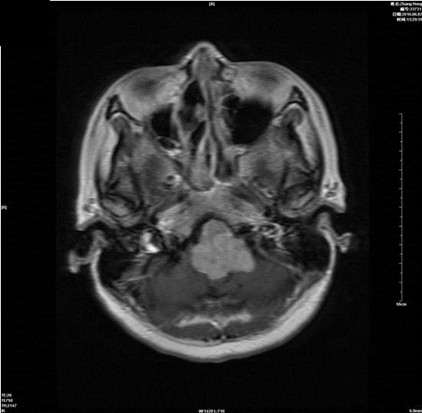

病例二:王**,男性,53岁。因做小脑肿瘤术后9年,头痛头晕,伴颈部疼痛、走路不稳半年入院。入院诊断:延颈交界血管网织细胞瘤。术式:后正中入路延颈交界区血管网织细胞瘤切除术。术后病理:血管网织细胞瘤。术后头痛头晕,颈部疼痛消失,走路平稳。

术前